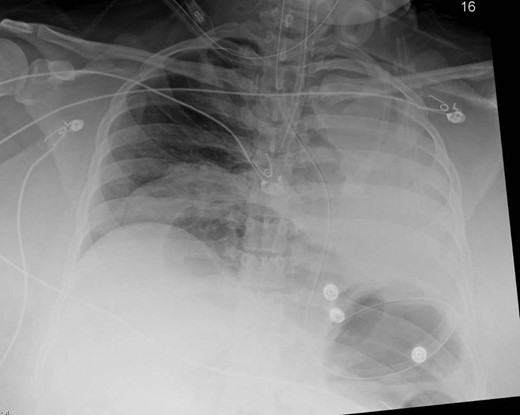

Upon arrival to our emergency department, the patient was febrile, obtunded and with a heart rate of 200 beats per minute. Her abdominal exam was consistent with peritonitis and her laboratory studies were consistent with shock and lactic acidosis. During evaluation by the surgical team, the patient required emergent intubation for progressive respiratory distress with ongoing fluid resuscitation for the treatment of shock. En route to the operating suite, the patient demonstrated rapid escalation in airway pressures, and cardiac arrest. After return of spontaneous circulation, a post-intubation chest radiograph demonstrated opacification of her left thoracic cavity and a coiled nasogastric tube within her stomach above her diaphragm (Fig. 2). Her abdomen became progressively more distended, concerning for abdominal compartment syndrome. With ongoing bag-mask ventilation, the patient was rushed to the operating room for emergent laparotomy.

Anterior–posterior chest x-ray obtained after intubation demonstrating bowel loops and a coiled nasogastric tube within the stomach, above the diaphragm and a coiled nasogastric tube above the diaphragm.